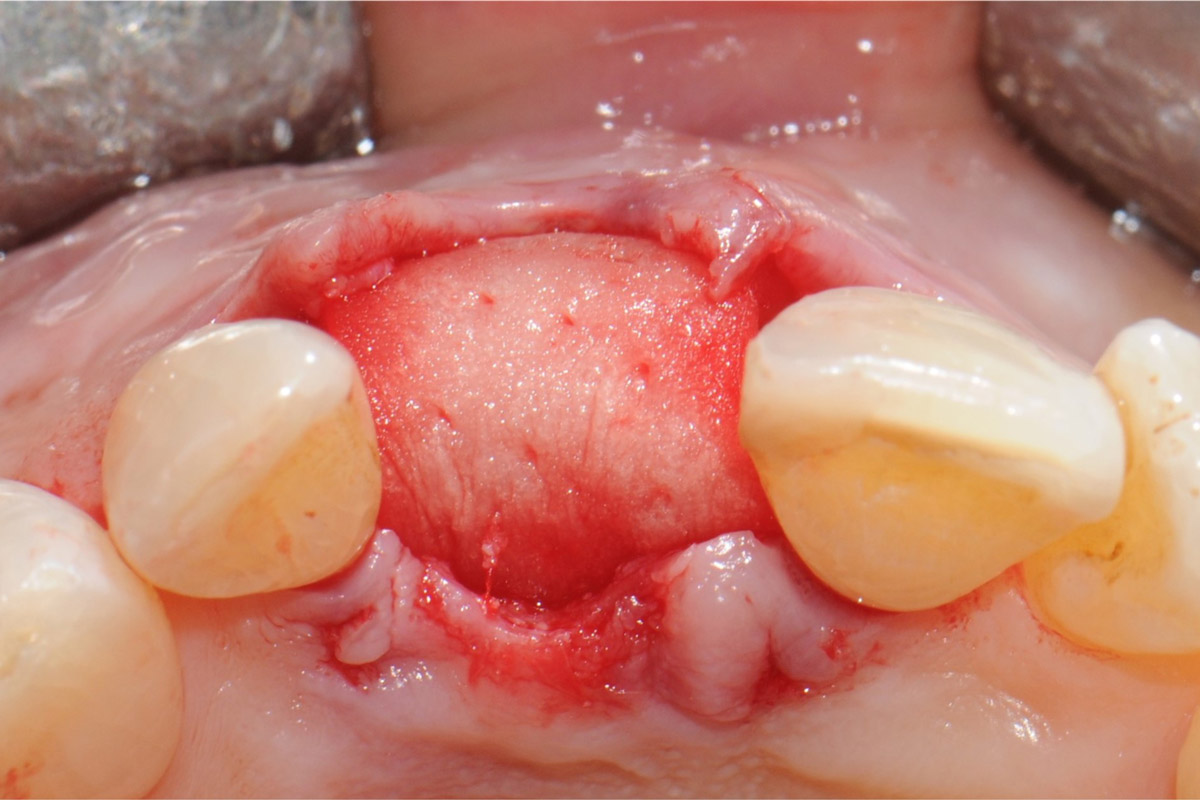

2/18 - Occlusal view showing buccal bone lossTooth extraction and socket sealing with mucoderm® - Dr. A. Rossi

5/18 - After atraumatic extractionTooth extraction and socket sealing with mucoderm® - Dr. A. Rossi

9/18 - mucoderm® used to seal the alveoleTooth extraction and socket sealing with mucoderm® - Dr. A. Rossi

10/18 - Coverage of the socket with mucoderm® adapted to the alveolar morphology. 2/3 of mucoderm® surface is covered by mucosal flapTooth extraction and socket sealing with mucoderm® - Dr. A. Rossi

12/18 - Occlusal view of the wound closureTooth extraction and socket sealing with mucoderm® - Dr. A. Rossi